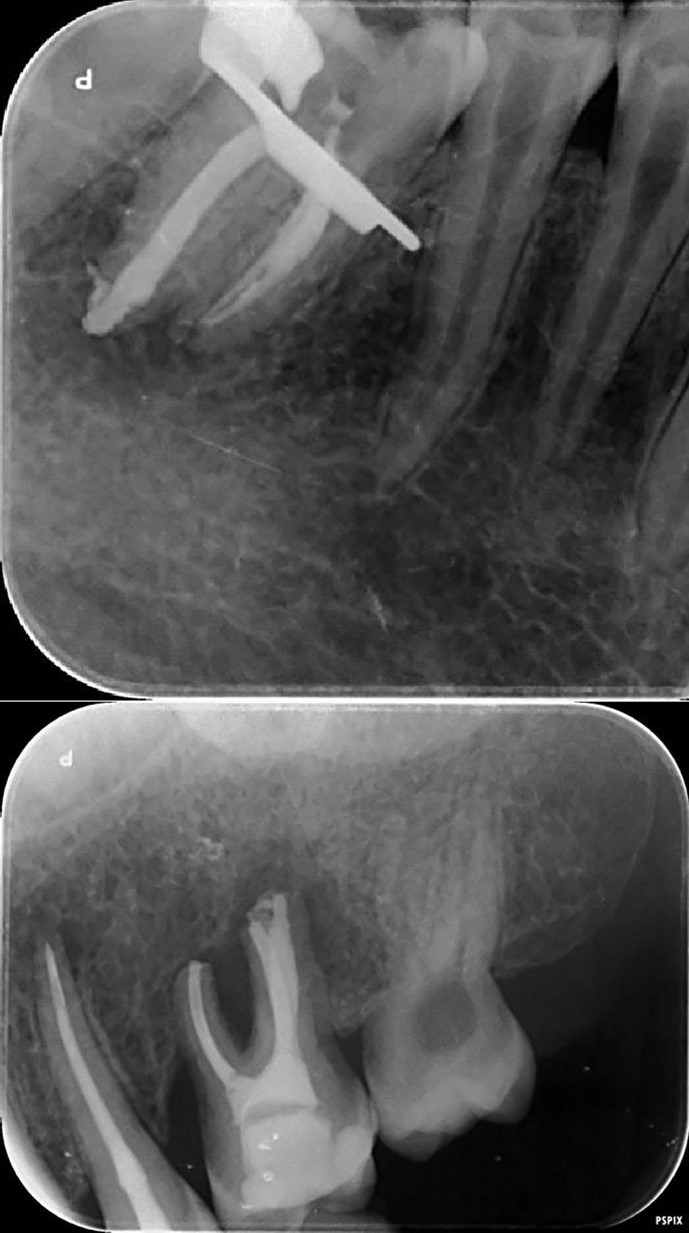

Complete healing of periapical lesions and treatment of teeth 26 and 16 with advanced endo-perio lesions posed challenges due to the patient’s delayed supplementation. In this case, surgical endodontic procedures and the extraction of teeth with advanced endo-perio lesions were considered risky because of the underlying metabolic healing impairment. Figure 3

Figure 3.6. 7, 8, 9, and 10 showing postoperative periapical radiographs of these endodontic treatments.